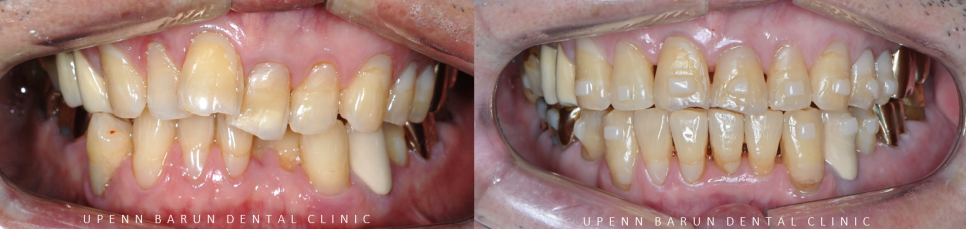

인비절라인교정 치료기간 23/3 ~ 24/8

인비절라인으로 교정 후

안쪽으로 쓰러져있고 삐뚤빼뚤했던 치아들이 가지런히 개선되고

구강 내 각자의 역할을 조화롭게 도와주어

기능적인 부분까지 회복 하실 수 있었어요 :)

교정완료 후에는

치아가 다시 안 틀어지도록

안쪽 치아에 유지장치를 제작해드렸습니다.

교정치료기간 23/3-24/8

79세의 고령 환자분이셨지만

탈부착이 가능하고

위생관리가 용이한 인비절라인으로 교정을 마무리 해드렸는데요,

교정 후에 치열이 가지런해지면서

잇몸관리가 수월해 빨갛게 부어있던 잇몸들이

선홍빛을 띄는 건강한 잇몸 색으로 돌아왔습니다.

심미적인 이유 뿐만 아니라

기능적으로도 많이 개선이 되어

환자분뿐만 아니라 원장님께서도 굉장히 뿌듯해 하셨습니다 :)